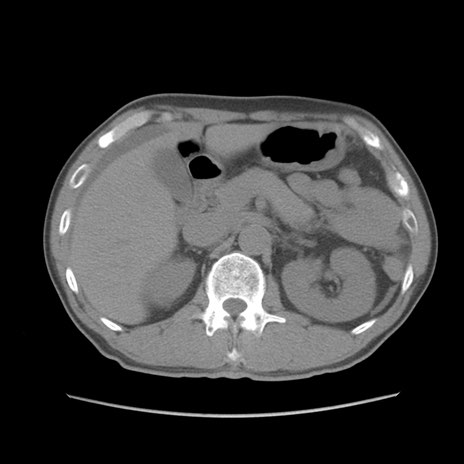

症例56 CT(横断像)